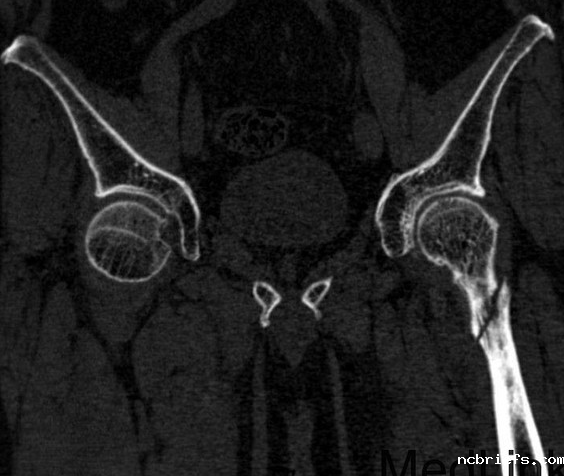

【gk-7000型号】便携式骨密度检测仪更方便检测左股骨粗隆间粉碎性骨折骨密度!

便携式骨密度检测仪更方便检测左转子间粉碎性骨折是生活中常见的骨折,其病因较为复杂。Once the disease affects the function of the left lateral fracture, it will produce different degrees of pain, swelling and other manifestations, resulting in the physical injury of the patient. We should be alert for functional changes between the left trochanter,粉碎性骨折的症状可采用以下方法治疗。